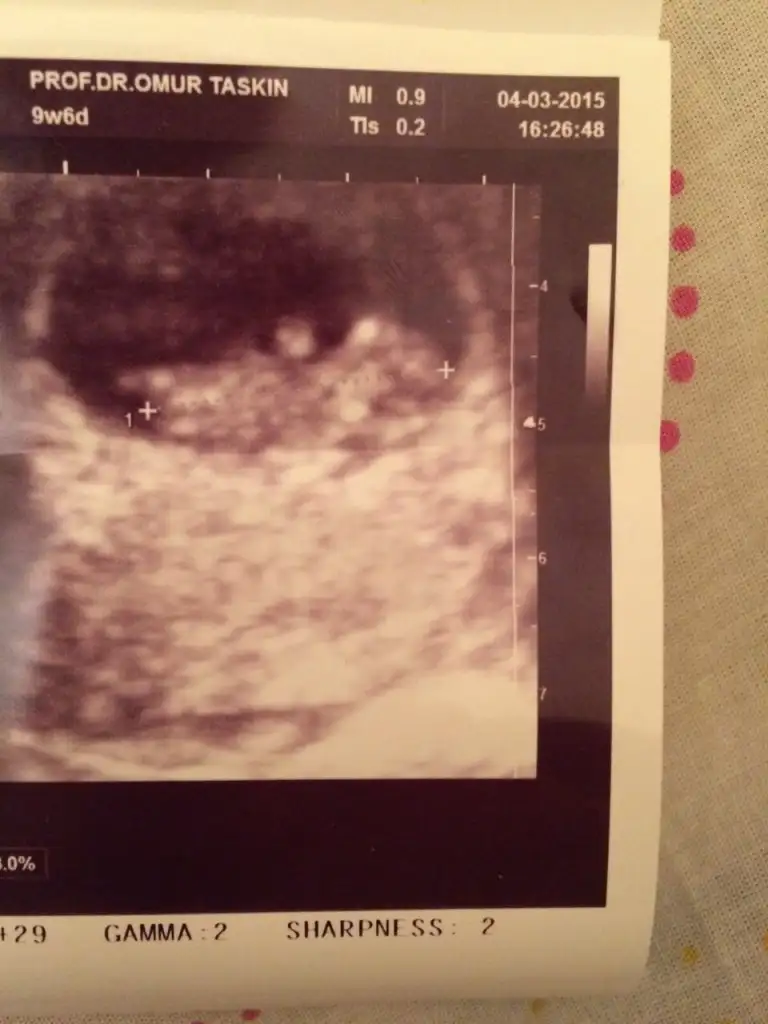

dr soylemeden siz gorun genital nub teorisi ( bebegin cinsiyeti)

Neden böle bi foto verdi kafasına bide ayaklarına bakıyom dedi normal dedi

kızlar benim bebeğimede bakar mısınız yorum yağar mısınız

kızlar 9+1 dedi cinsiyet tahmin edebilir misiniz